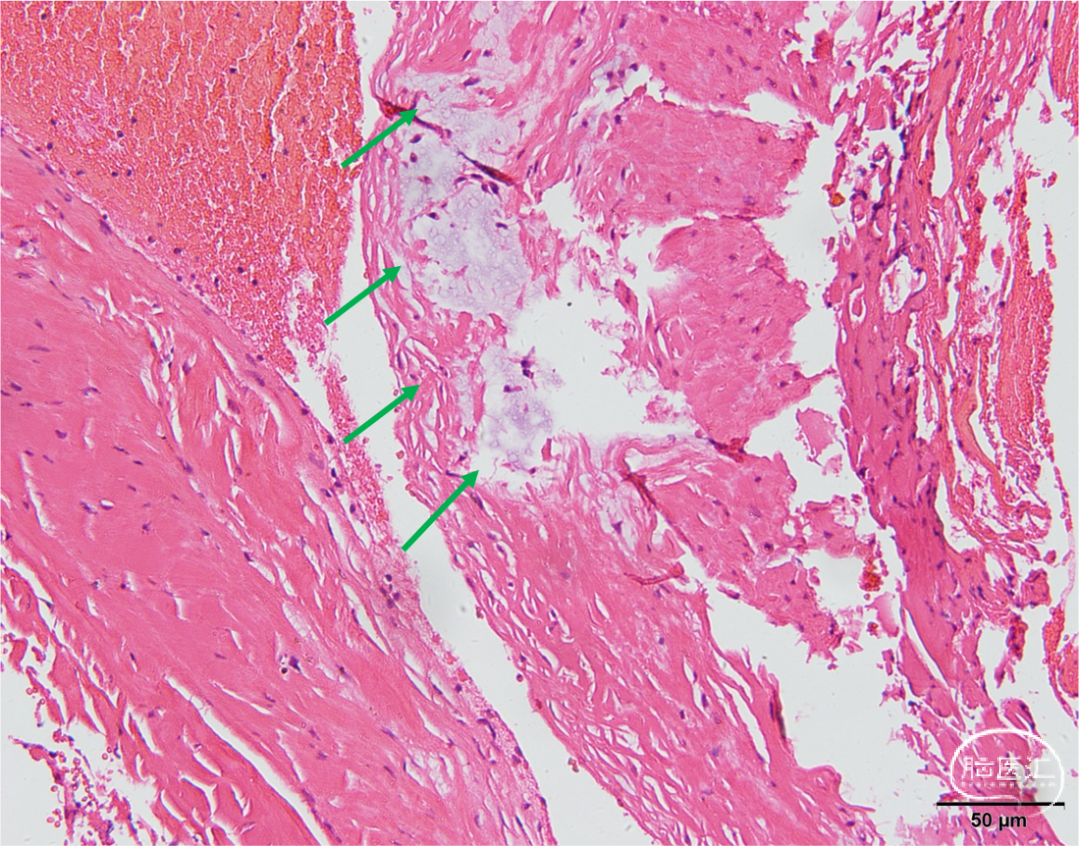

(右侧大脑前动脉动脉瘤)囊壁大部分为排列致密的纤维和胶原纤维,局部可见玻璃样变性。另见有灶性的黏液样变性,其内可见数个星状细胞,提示粘液瘤累及可能(图5)。(右侧大脑中动脉动脉瘤)镜下仅为排列致密的纤维和胶原纤维组织。术后3个月复查头颅MRA,动脉瘤完全不显影。

图5 右侧大脑前动脉动脉瘤切片镜下图像,见动脉瘤壁局部玻璃样变性及黏液样变性,纤维结构被破坏(绿色箭头)。讨论